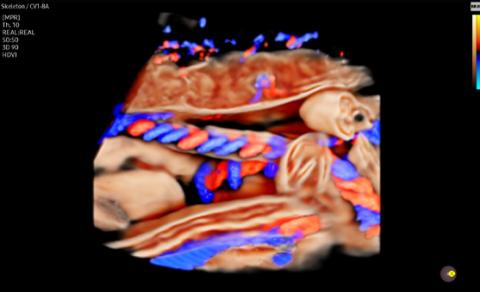

CrystalLive™ in 3D/4D provides users with more realistic and high-resolution images. It outdoes conventional 3D imaging technologies in terms of viewing small parts and lighting effects. In addition, you are able to see 3D anatomy with more realistic depth perception, and can visualize the internal and external structures at once.

CrystalVue™ is an advanced volume rendering technology that enhances visualization of both internal and external structures in a single rendered image using a combination of intensity, gradient and position.

RealisticVue™ ¹ displays high resolution 3D anatomy with exceptional detail and realistic depth perception. User selectable light source direction creates intricately graduated shadows for better defined anatomical structures.

CrystalVue Flow™ ¹ is a volume rendering technology that provides additional information of blood flow morphology based on the CrystalVue™ features that visualizes the internal structures by projecting the 3D data, providing better understanding in the anatomic structures and surrounding vascular vessels.